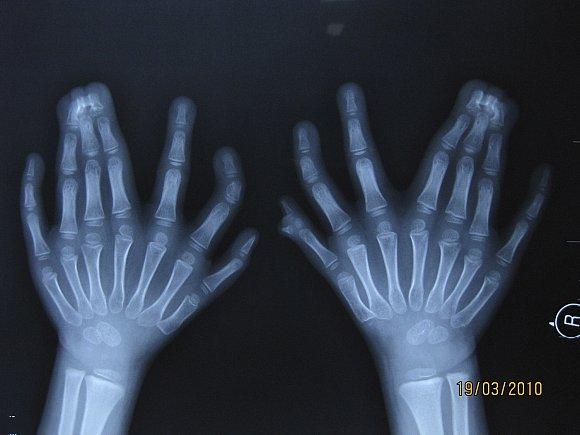

• ( 30 أصبع ) لدى فتى صيني !! سبحان الخالق

30 أصبع ) لدى فتى صيني !!

الفتى يبلغ من العمر 6 أعوام ويملك 14 أصبع في اليد و16 في القدم

سيجري عملية بأحد المستشفيات لاستئصال الأصابع الزائدة